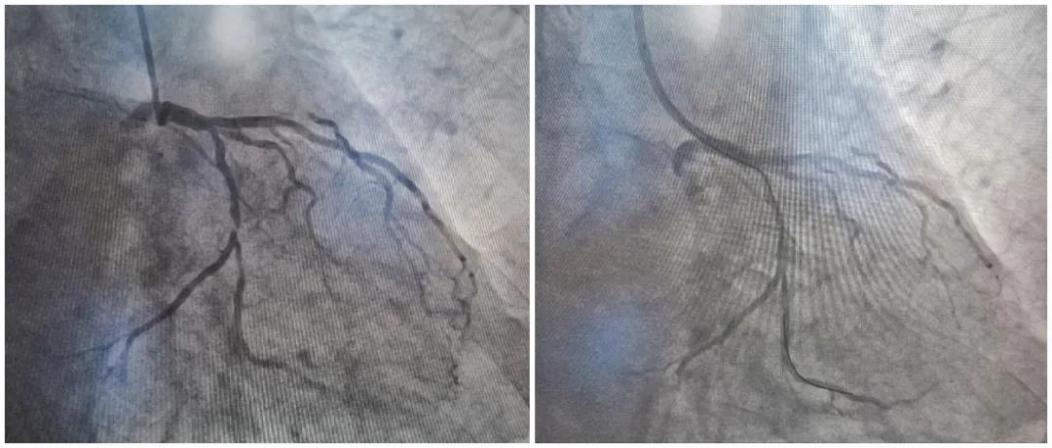

四、2021.01.27我院第一台急诊PCI术:

由周亚峰副院长和张强主任医师为患者实施经桡动脉急诊PCI手术。顺利开通闭塞血管,血管血流通畅,患者安返病房。术后,患者胸闷症状明显改善,生命体征平稳。

六、2021.04.22我院第一例OCT指导下的生物可吸收支架植入术:

我院心血管内科周亚峰副院长主刀,顺利完成了苏州市首例OCT指导下的生物可吸收支架植入术(又称生物可降解支架,NeoVas支架)植入术,这标志着我院冠心病介入治疗率先迈入了精准化、先进化的时代。